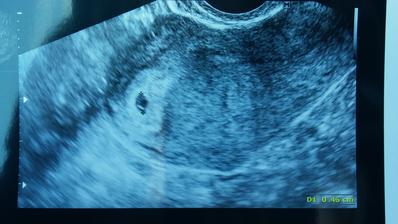

Kontrola dopadla dobře mimi zrovna spinkalo takže jsme si ho mohli krásně prohlédnou a změřit no a taky nás nechal nakouknout mezi nožičky a čekáme kluka